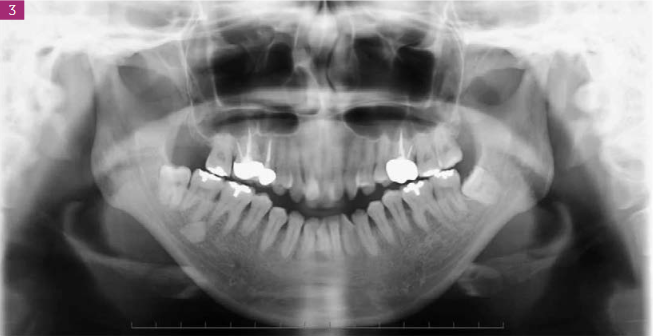

Streszczenie: Wprowadzenie. Niewiele jest publikacji opisujących leczenie zgryzu otwartego z dysfunkcją stawu skroniowo-żuchwowego metodą intruzji zębów trzonowych za pomocą miniśrub. Opis przypadku. Niniejsze doniesienie przedstawia 42-letnią Japonkę z poważną wadą szkieletową klasy II ze zgryzem otwartym i z dysfunkcją stawu skroniowo-żuchwowego. Rezonans magnetyczny obu stawów skroniowo-żuchwowych przed leczeniem wykazał zmiany zwyrodnieniowe i doprzednie przemieszczenie krążka stawowego bez redukcji w obu stawach skroniowo-żuchwowych. Przed leczeniem ortodontycznym zastosowano szynę stabilizującą i dokonano obustronnej ekstrakcji górnych i dolnych zębów przedtrzonowych. Od strony podniebiennej w szczęce umieszczono miniśruby, aby uzyskać intruzję zębów trzonowych i uniknąć utraty zakotwienia. Usunięto również pierwszy lewy trzonowiec górny, aby poprawić relację trzonowców i linię środkową łuku zębowego. Uzyskano prawidłowy nagryz pionowy i poziomy z relacją trzonowców w kl. I Angle’a, oraz zbieżność lini środkowej górnego i dolnego łuku zębowego. W 2-letnim okresie obserwacji uzębienie pacjentki pozostało stabilne, a stawy skroniowo-żuchwowe nie powodowały objawów. Wnioski. W przypadku poważnej wady szkieletowej klasy II ze zgryzem otwartym możliwa jest intruzja zębów trzonowych z zastosowaniem miniśrub.